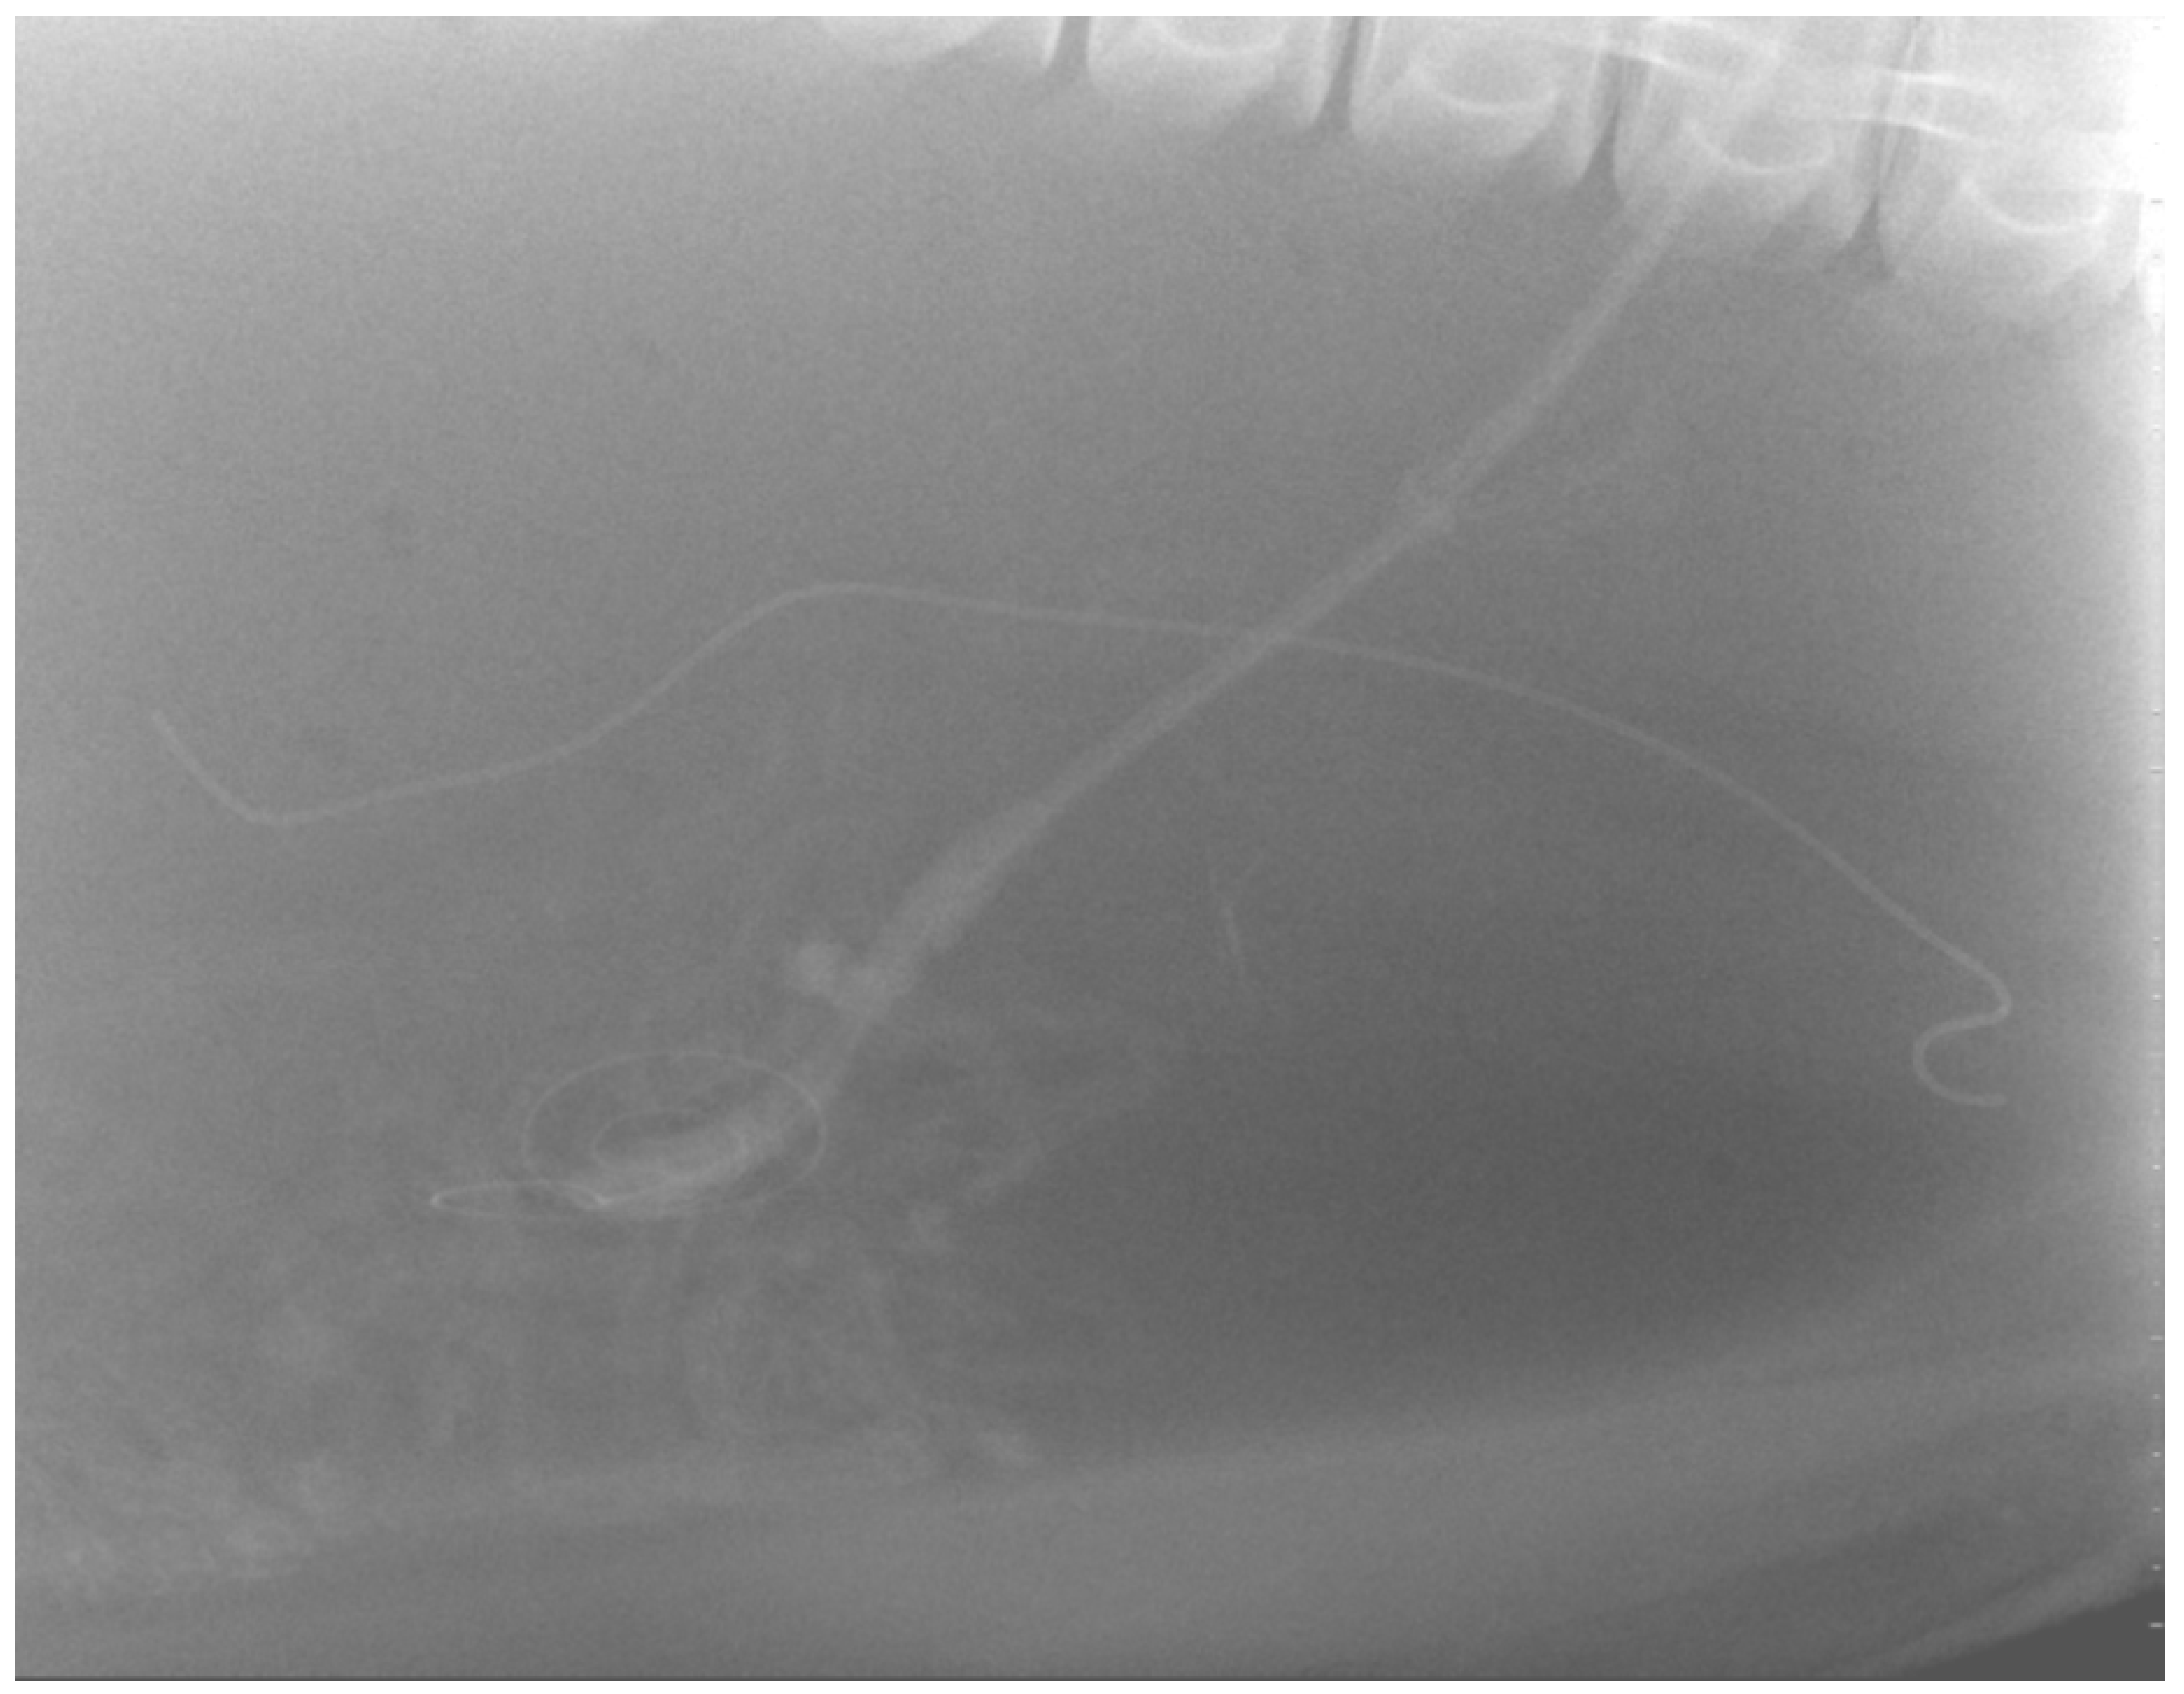

The peel-away-sheath was removed, and the PD catheter was sutured in place to the skin of the right flank, using 2-0 Maxon™ (Tyco Healthcare). A subcutaneous catheter tunnel was not performed to minimize injury to the dense blubber layer. A lateral abdominal radiograph was taken to assess the position of the PD catheter (Figure 2).

Figure 2. Lateral abdominal radiograph with dolphin in left lateral recumbency, head to left, showing curled PD catheter in ventral abdomen with external tubing extending caudodorsal and ureteral stent in left ureter.